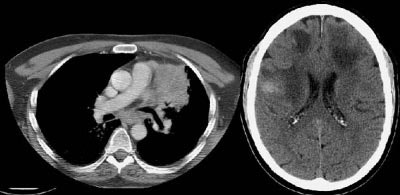

Example of brain metastases: This patient with non-small-cell lung cancer presented with left vocal cord paralysis. He did not have any neurological complaints. A central mass in the left lung was obstructing the left upper lobe bronchus (left image -- also note N2 subcarinal adenopathy). A head CT was requested by the patient's health care provider as part of the evaluation for his vocal cord paralysis and demonstrated multiple brain metastases, one of which is likely hemorrhagic (right fronto-parietal cortex).